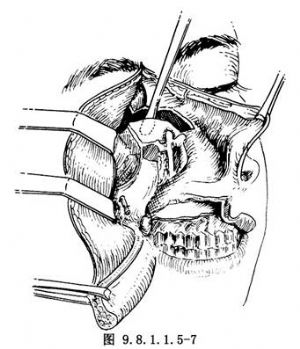

病變範圍較小,主要位於鼻腔上部和篩區,鼻底和上頜竇外下部未受侵犯者,爭取保留上齶,這對於減少口腔和咽部向顱底的污染,及保存病人術後口腔功能都有利。此術式基本採用Sisson's篩骨及鼻腔上頜側壁大塊切除術式。做鼻側切開術,切口起自眉弓內端,向下順鼻側過鼻翼而至鼻翼外腳,切開鼻前孔,分離鼻骨,連同鼻翼前上翻轉,充分顯露鼻腔(圖9.8.1.1.5-5)。切斷內眥韌帶,沿眶內壁分離紙樣板,探查紙樣板有無骨質破壞。電燒切斷篩前動脈,分離達眶尖,上方與顱內切開線相連。分離淚囊,切斷鼻淚管,向外上牽引眶內容,分離眶底至眶尖。切開上脣,分離並翻開頰側軟組織瓣。於尖牙窩區鑿骨窗,探查上頜竇,若證明其底部及外側壁可以保留,將竇骨黏膜分離連於竇內上角。於眶下孔處切開眶下壁骨板達眶尖。於鼻底處切開鼻腔側壁達翼突,完成外側及下方遊離。下一步是暴露鼻腔上部與顱內切開線。若鼻腔上方術野顯露尚不夠,可分離對側鼻骨,切開鼻中隔,全翻鼻錐而擴大術野。於中部橫形切開鼻中隔,並於前後向上切開與顱內切開線相接(圖9.8.1.1.5-6)。至此,除師竇及鼻腔側壁後部尚與蝶骨體及翼突連接外,腫瘤四周全部遊離。用彎剪經顱內後方切開線伸入,剪開後方上部連接,並用手指向下推壓已遊離之前顱底區,使標本向前下移位。再用彎剪,由面部術區伸入後方,剪開標本後部下方之連接,全部標本即可由面部取出(圖9.8.1.1.5-7)。後篩區與蝶體和眶尖連接部分常不能一次徹底切下,需要局部再次修切。